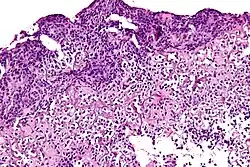

![]() |

Lepromatous leprosy | Skin biopsy showing epidermal atrophy and multiple dermal infiltrates. | Category: Histopathology of leprosy | Leprosy |